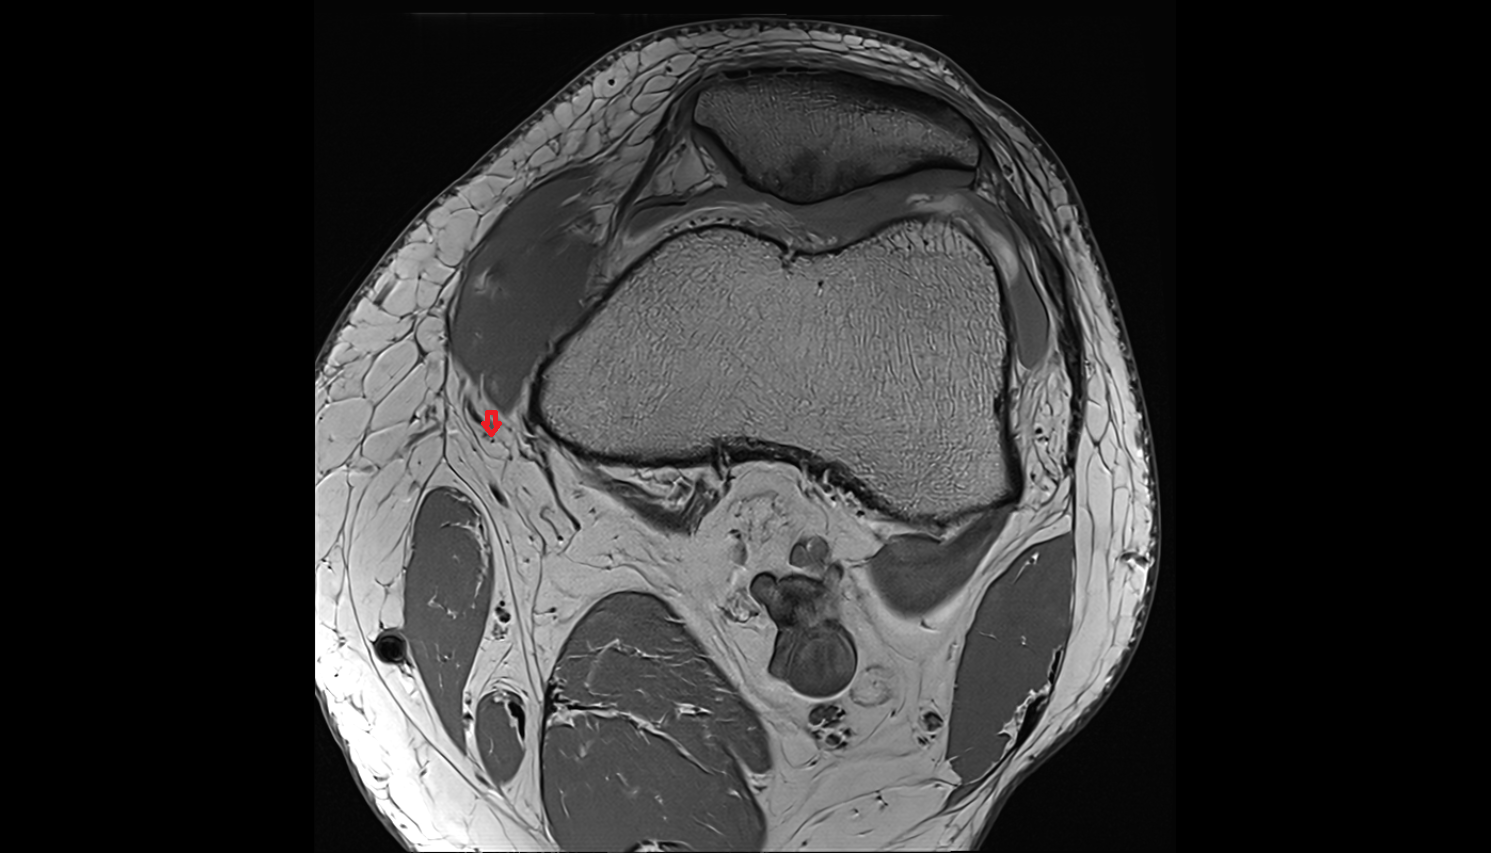

- Medial collateral ligament

- Medial meniscus

- Lateral meniscus

- Knee Joint